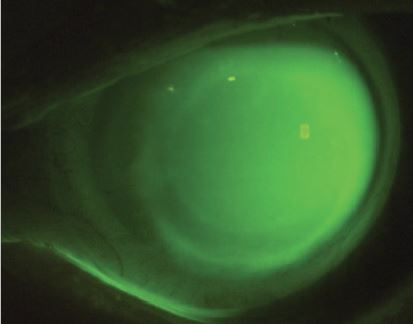

لنزهای Rose K (رز کی )برای کراتوکونوس | لنز تخصصی برای قوز قرنیه

کرتوکونوس: بیماری قرنیه که اگر زود تشخیص داده نشود، پیوند تنها راه خواهد بود